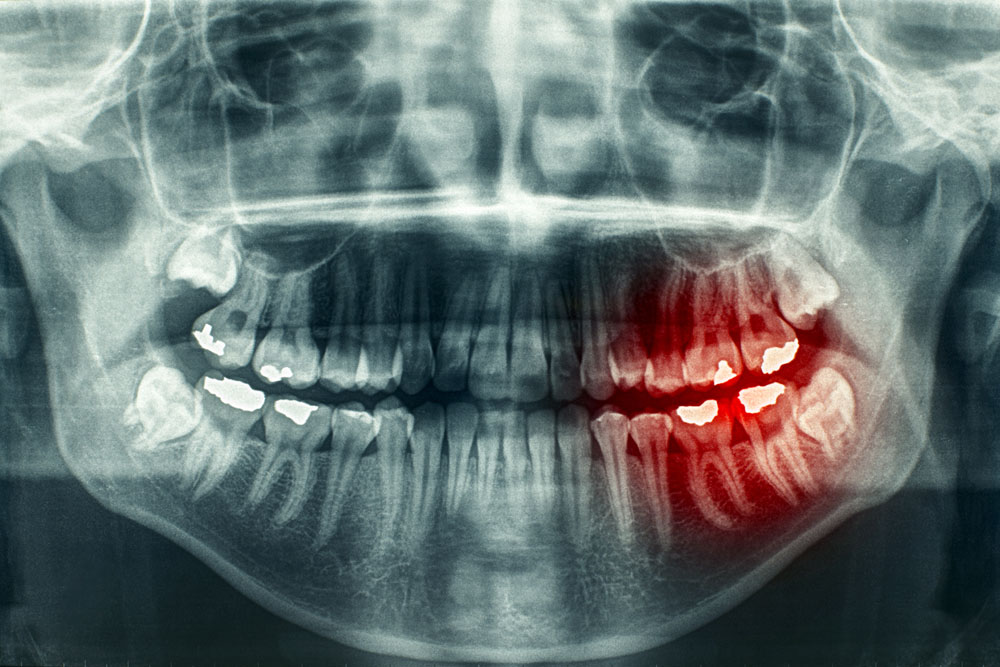

牙疼痛的时候可以杀神经吗 (牙痛神经痛可以根管治疗吗)

牙疼放了杀神经药还疼怎么缓解,牙痛神经痛可以根管治疗吗

那么,大家有过牙痛的经历么,牙痛不算病,痛起来要人命,每当牙痛难忍时,怎么办呀。

医生告诉你:“要杀神经。”

若有上述顽固性、难治性、反反复复、持续难忍的疼痛疾病时,请想到还有疼痛科可就诊,那里有一种技术是杀神经。

就如:牙痛,杀神经。